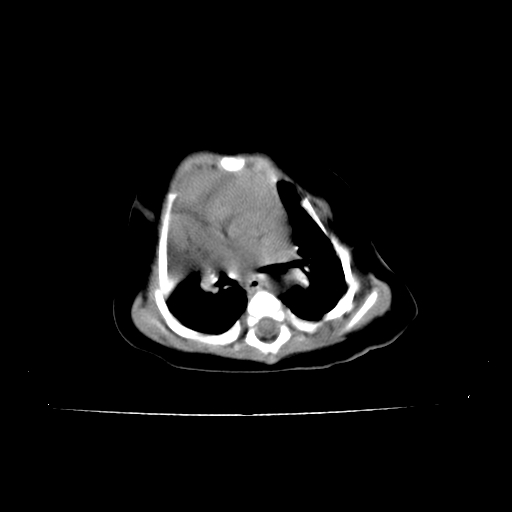

以下是引用影像之路在2009-5-8 15:46:00的发言:[br]1)胸廓畸形。2)考虑两肺感染性病变,并右肺上中叶肺不张;建议抗炎治疗后复查。3)胸腺肥大。4)前上中纵隔占位性病变待排;建议追踪复查。

以下是引用余辉在2009-5-8 8:44:00的发言:[br]鸡胸,胸腺肥大,双肺感染性病变,结合病史支原体肺炎可能性大